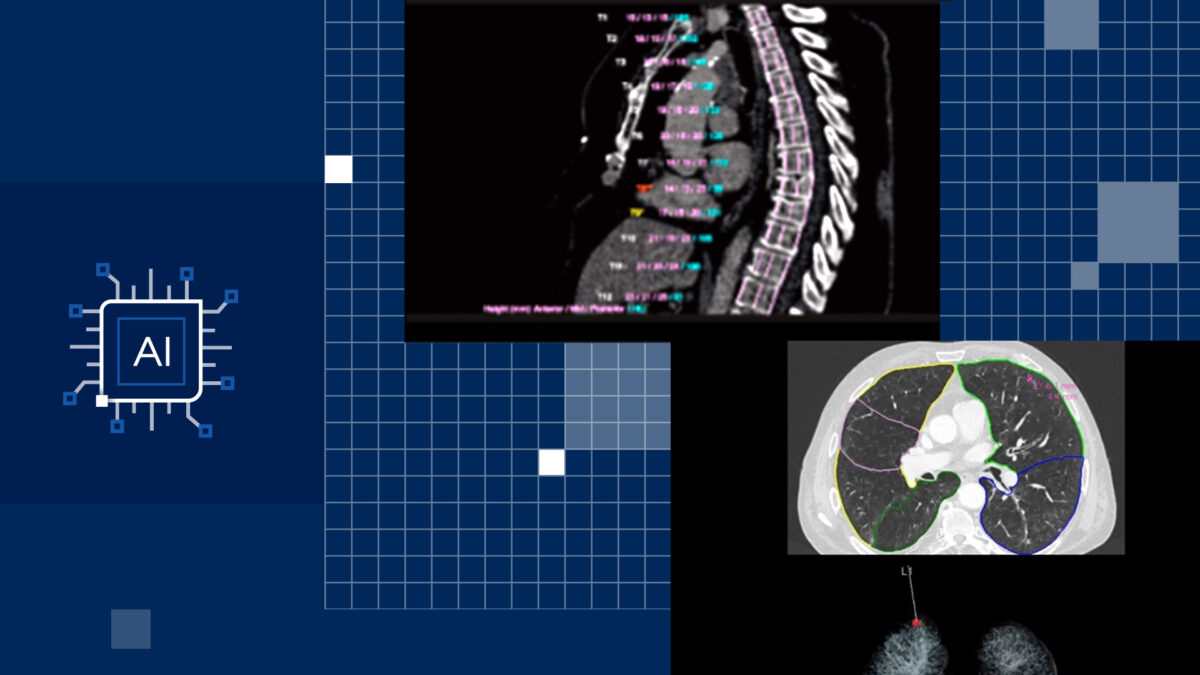

AI-Rad Companion is a set of AI algorithms that helps clinicians speed up diagnosis and therapy. Using a CT or MRI scan of a patient about to undergo cancer treatment, the AI almost instantly can visually segment out anatomical structures and color-contour, or “shade,” the cancerous cells of a tumor to be targeted for radiation, leaving healthy cells untouched.

Using Intel’s OpenVINO™ technology, an open source toolkit that can be used to accelerate AI inferencing, AI-Rad Companion’s algorithms have been trained to recognize organs and anatomical data. With that information, the AI can recognize even the smallest abnormality and alert the physician to where and what it is. It can help the doctor diagnose certain diseases in the lungs, brain and prostate, and neurodegenerative diseases like Alzheimer’s. This can reduce the cost of care because it’s speeding up the treatment planning for patients.

The AI-Rad Companion software assists the clinician in identifying, measuring, characterizing and quantifying abnormalities, which can reduce a clinician’s diagnostic interpretation time when reviewing complex imaging cases. And because Xeon Scalable processors are designed for both cloud and server-based applications, medical facilities using AI-Rad Companion can choose which is the most efficient way to access the software.